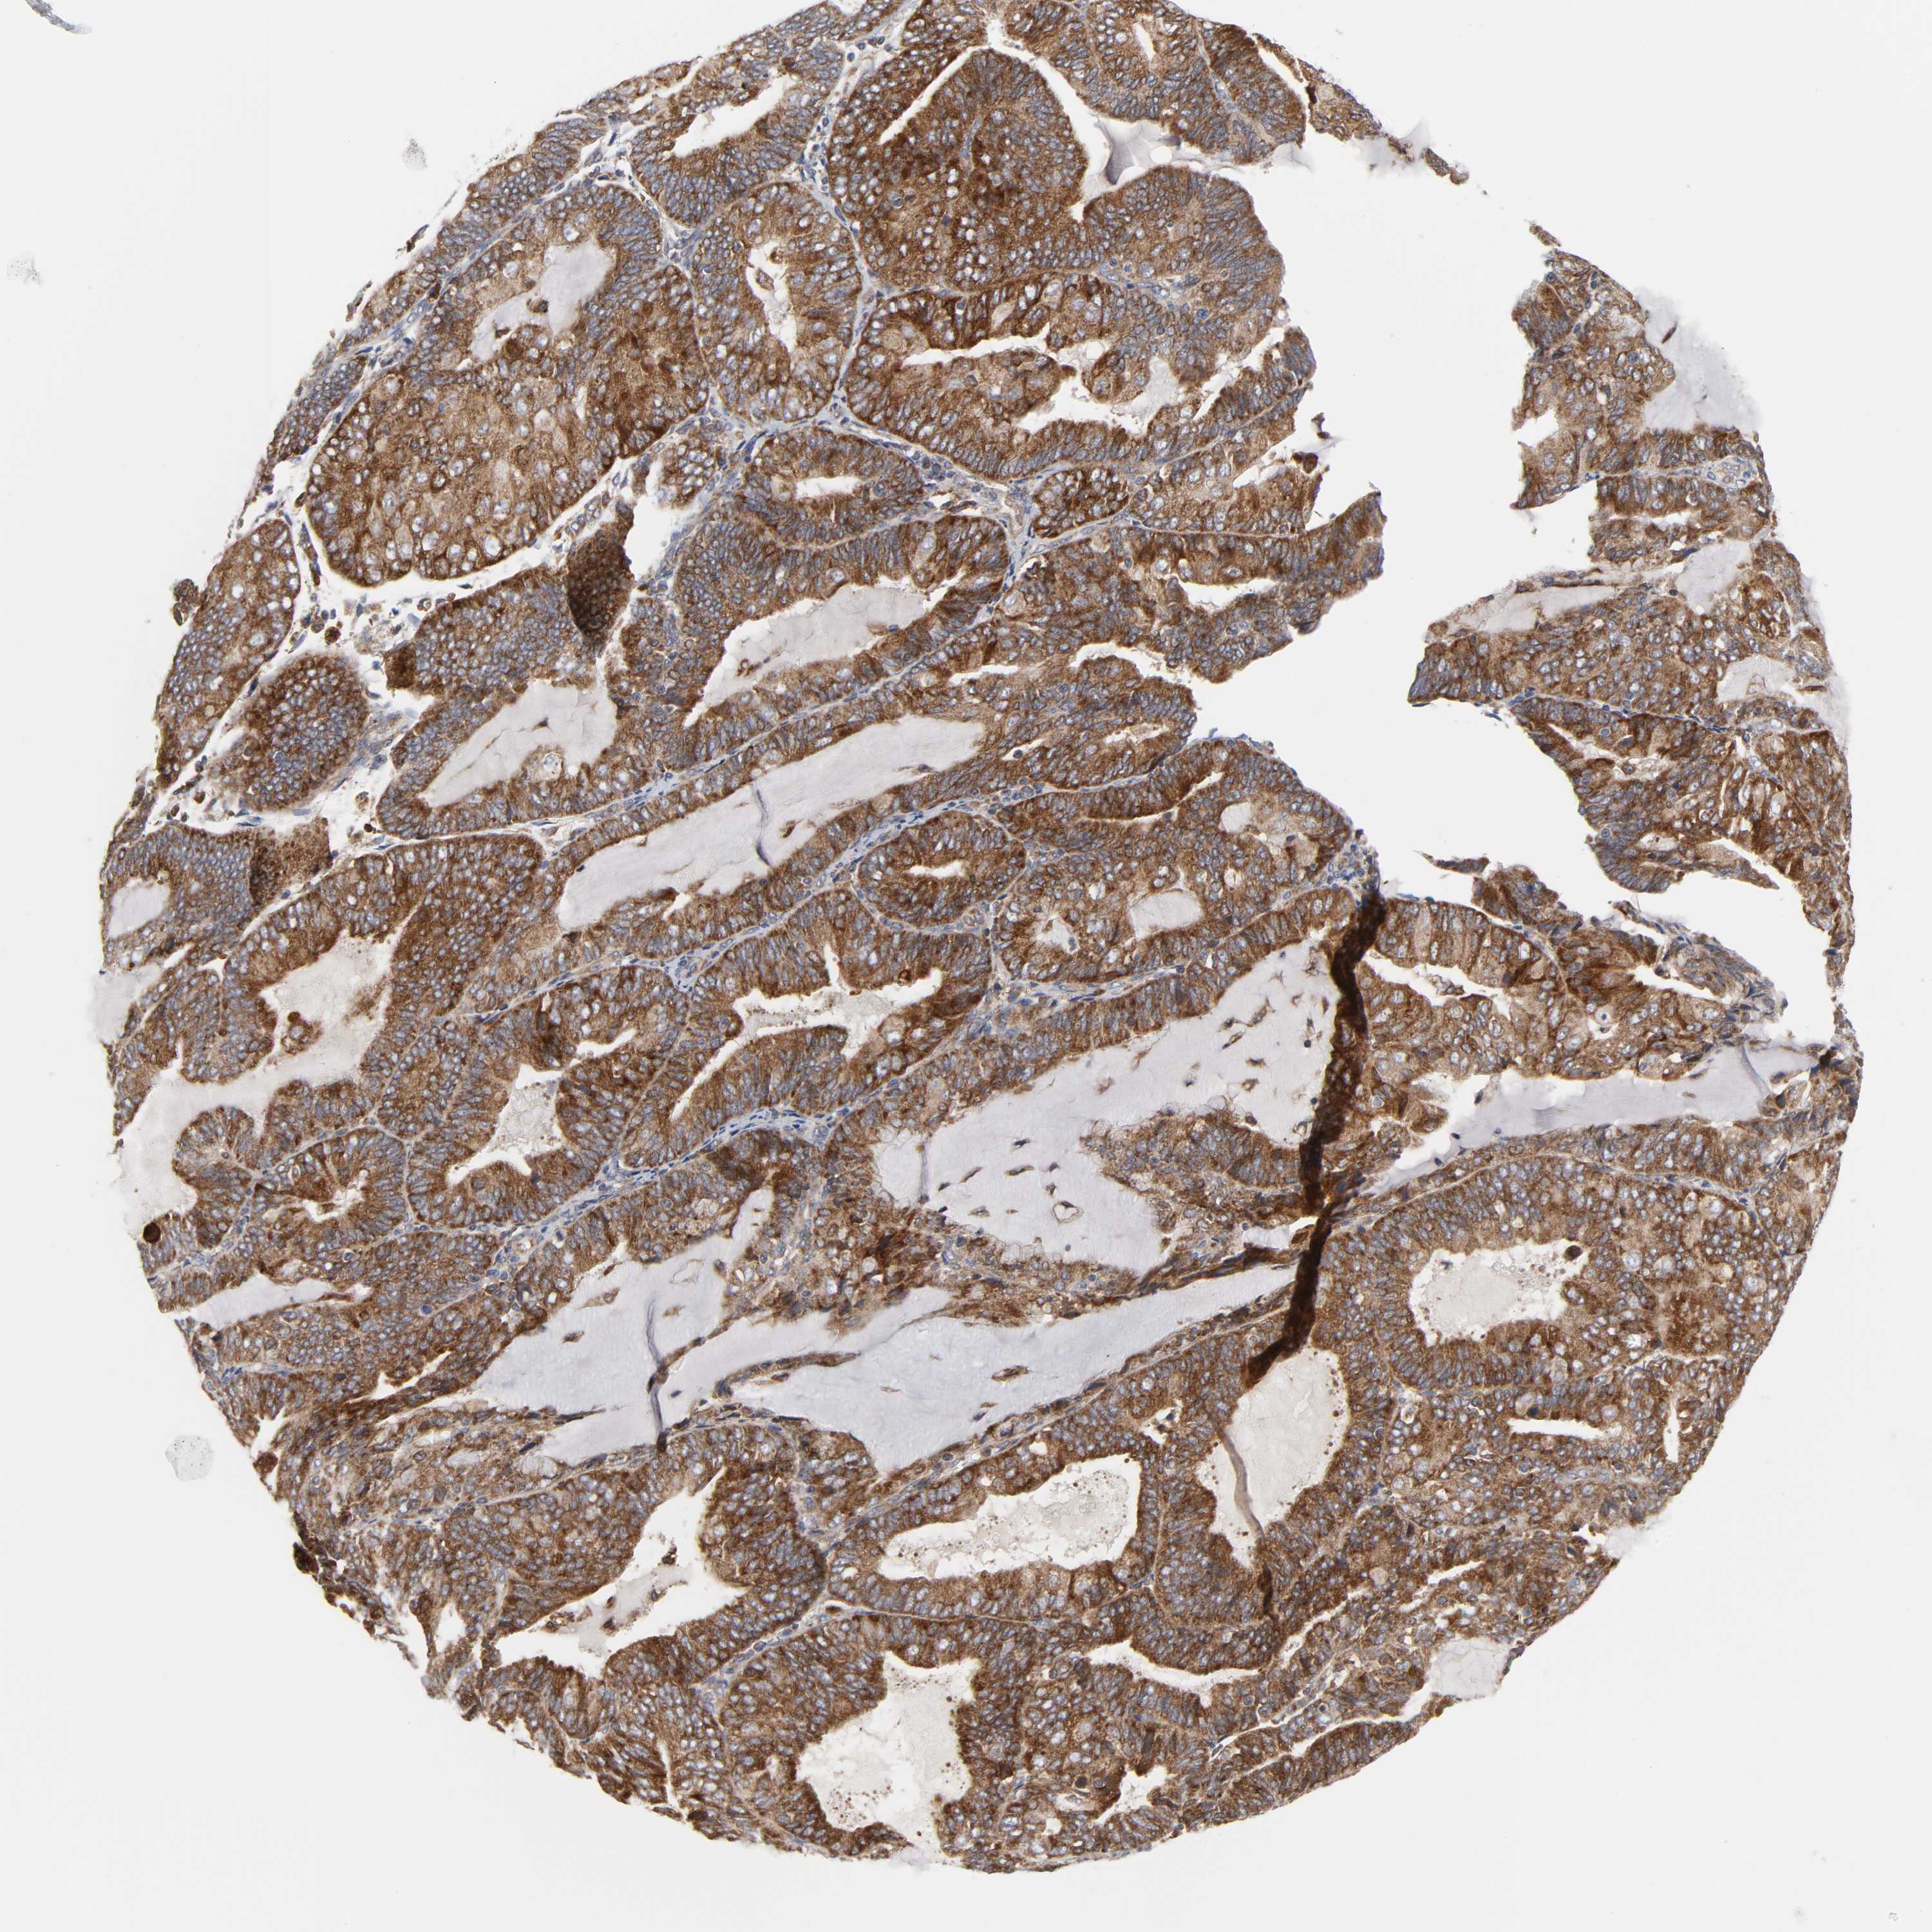

ENDOMETRIAL CANCER - Protein expressioni

A mouse-over function shows sample information and annotation data. Click on an image to view it in a full screen mode. Samples can be filtered based on level of antibody staining by selecting one or several of the following categories: high, medium, low and not detected. The assay and annotation is described here.

Note that samples used for immunohistochemistry by the Human Protein Atlas do not correspond to samples in the TCGA dataset.

Antibody stainingi

Antibody staining in the annotated cell types in the current human tissue is reported as not detected, low, medium, or high, based on conventional immunohistochemistry profiling in selected tissues. This score is based on the combination of the staining intensity and fraction of stained cells.

Each image is clickable and will lead to virtual microscopy that enables deeper exploration of all samples and also displays staining intensity scores, fraction scores and subcellular localization as well as patient and tissue information for each sample.

Antibody HPA027878

Antibody CAB004206

Staining

High

Medium

Low

Not detected

Intensity

Strong

Moderate

Weak

Negative

Quantity

>75%

75%-25%

<25%

None

Location

Nuclear

Cytoplasmic/membranous

Cytoplasmic/membranous,nuclear

Adenocarcinoma, metastatic, NOS